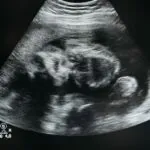

Pregnancy is a beautiful journey filled with joy and anticipation, but it can also lead to unexpected surprises—like an umbilical hernia. If you’re scratching your head wondering what that is, you’re not alone. Many new

As pregnancy progresses, every mom-to-be experiences that magical moment when her baby drops—like a surprise party that everyone’s been waiting for. This delightful shift signals the baby’s readiness for the grand entrance, and it’s a